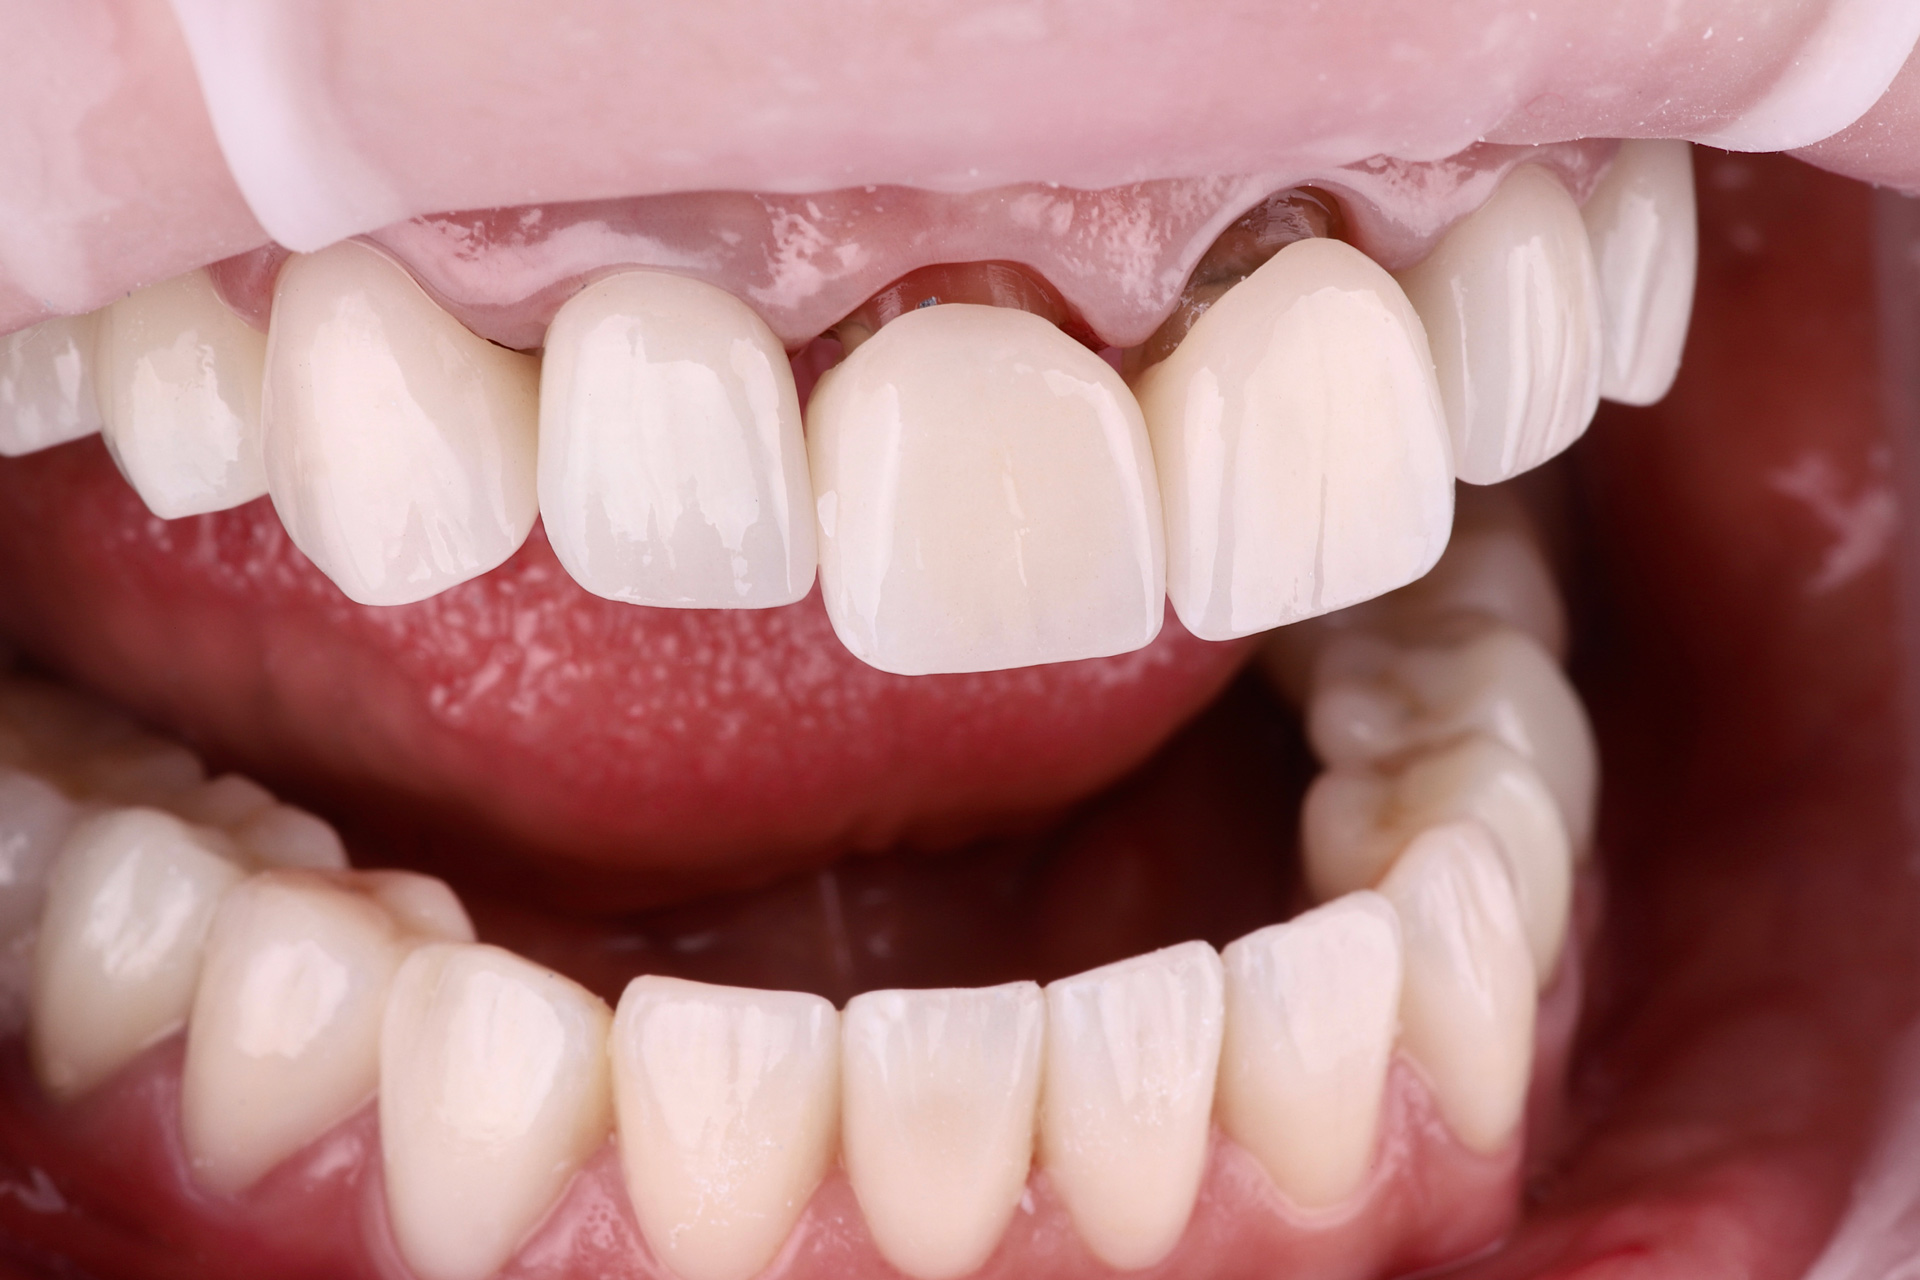

І настала війна… Після 1,5 року ми зустрілись знову. А частини тимчасових зубів вже не було, але положення щелеп та імплантанти збереглись. Тому дуже швидко перевели роботу з тимчасових коронок на постійні. Загалом було встановлено всі види ортопедичних конструкцій: коронки, вініри та керамічні накладки.